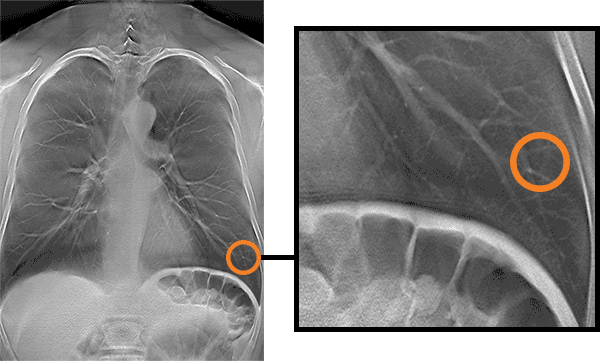

Corte de imagem obtida por meio de tomossíntese digital mostrando uma patologia/múltiplos cortes mostrando uma patologia